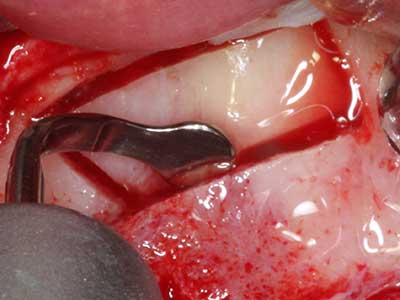

Indication: Bone grafting

Autologous bone transplants are used in the form of blocks, shells, rings and are also combined with bone replacement materials as chips. If the implant site is prepared at the same time as the augmentation, various bone filter systems have proven effective for collecting the resulting bone chips. As an alternative, the implant site can be prepared using a low-speed device without irrigation. If an implant is not inserted, bone chips can be harvested from the periphery with bone scrapers. This is also possible with piezo surgery using specialized attachments that yield higher-quality bone chips compared chips harvested with round drills, as has been confirmed in a study comparing the two methods (Chiriac, Herten et al. 2005).

Piezo surgery has additional advantages when harvesting bone blocks. In addition to the high precision with osteotomy described above, the use of the thin saw tips specifically minimizes loss of material. Greater loss of material during harvesting can be expected with the thicker instrument tips, particularly when using Lindemann drills (Lakshmiganthan, Gokulanathan et al. 2012). The basal separation, which is necessary particularly for retromolar block transplants, is simplified by specially designed rectangular saws, with the result that piezo surgery is viewed as a precise, simple and safe procedure for harvesting retromolar bone blocks (Happe 2007) (Fig. 1-12).